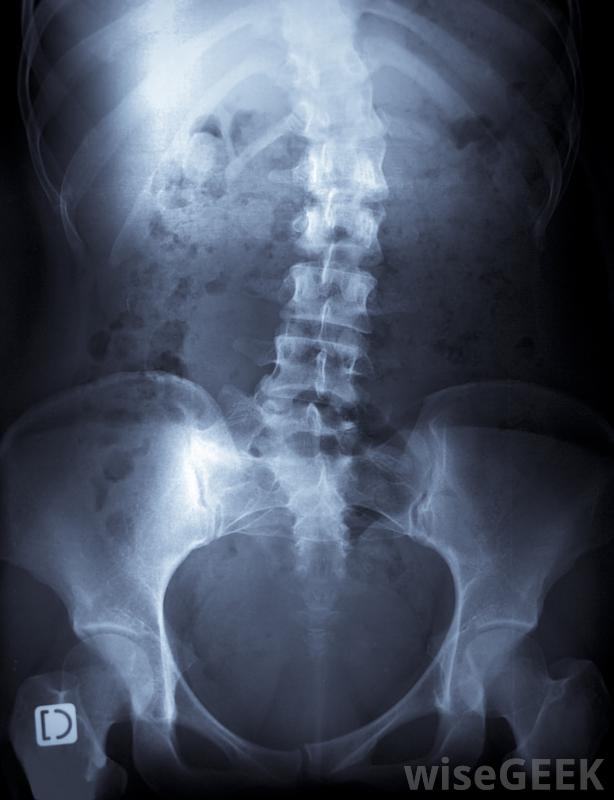

脊柱侧凸是脊柱的一种侧弯或侧弯,它是一列被称为"椎骨"的小骨柱,相互堆叠在一起;它从颈部后部开始,一直延伸到臀部顶部。虽然每个脊柱都有自然的前后曲线,但如果在青春期脊柱生长时形成了侧弯,则可以使用脊柱侧凸后支具来矫正曲线。如果没有矫正,明显的曲线可能会导致不平衡、肌肉无力、疼痛,甚至极端情况下会干扰呼吸。